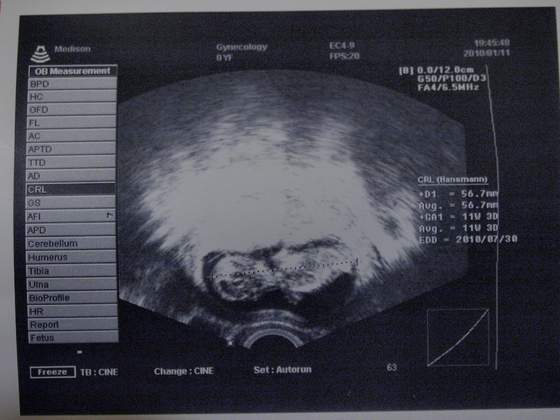

ja po wczorajszej wizycie też mam mniej nerwów i oczywiście wyszłam z rogalem na buzi ;-) nie spodziewałam się usg, ale miałam i na dodatek zdjęcie wycyganiłampani średnio chciała dać, bo mówi, ze za pare dni genetyczne i dostane mnostwo slicznych zdjec, ale jednak dala :-)

Maluch ma 56,7 mm czyli troszke wiecej niz sie spodziewalam i termin tez sie skraca jesli wciaz bedzie tak rosnac, bede mama lipcowa...